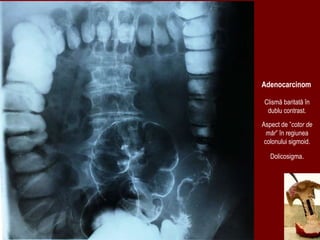

Clismă baritată în

dublu contrast.

Aspect de ”cotor de

măr” în regiunea

colonului sigmoid.

Dolicosigma.

Adenocarcinom